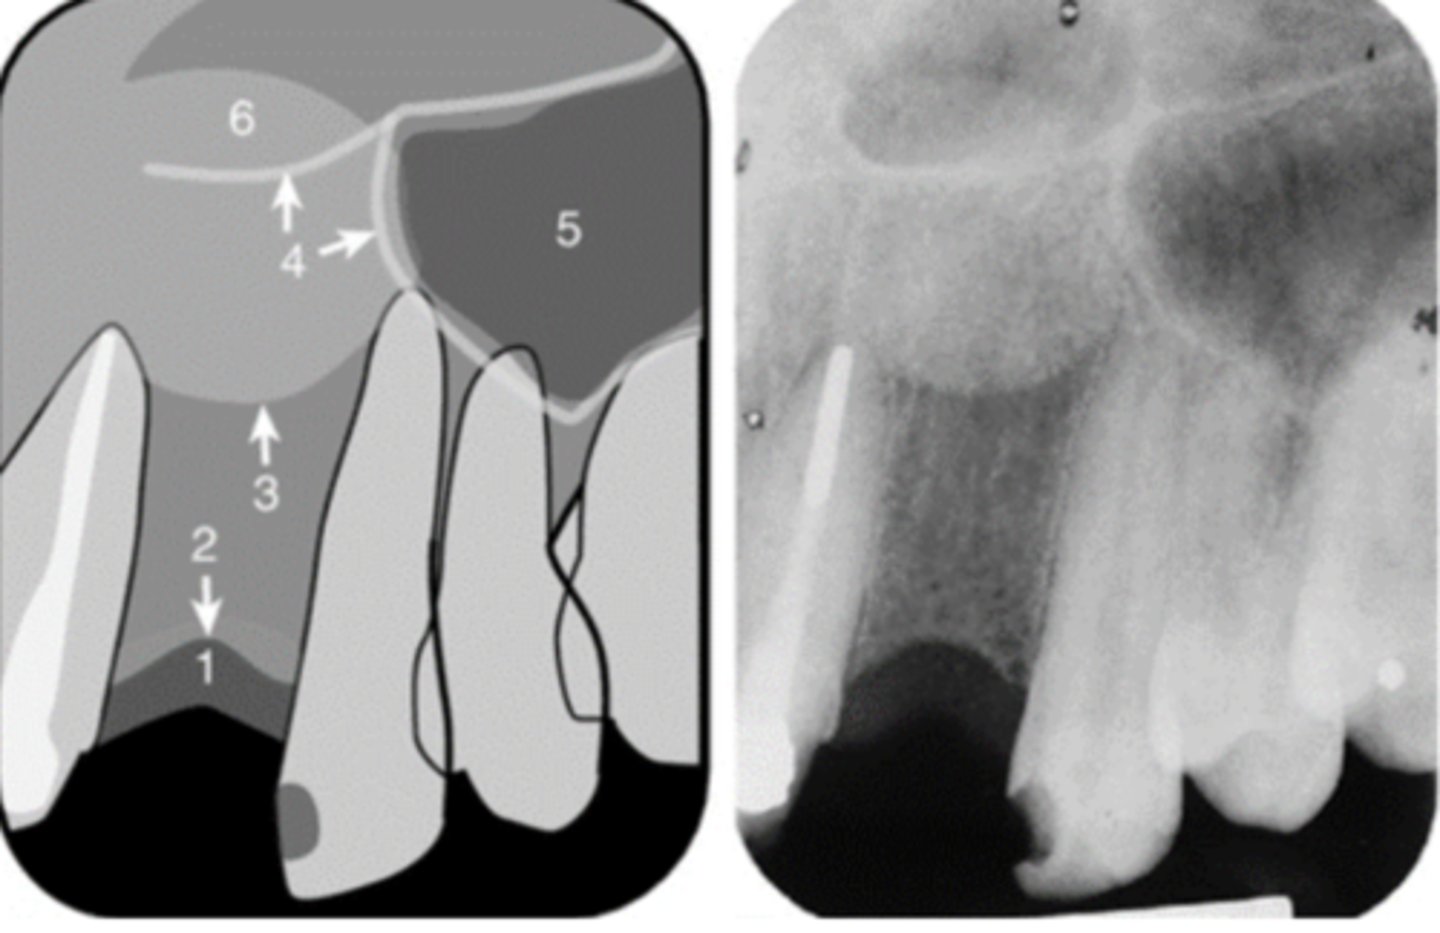

41

New cards

Floor of the maxillary sinus

Name the line indicated by arrows labeled #2.

<p>Name the line indicated by arrows labeled #2.</p>

42

Hamulus

Name the elongated radiopacity indicated by #5.

<p>Name the elongated radiopacity indicated by #5.</p>

43

Lateral pterygoid plate

Name the large radiopacity with a rounded inferior margin indicated by #4.

<p>Name the large radiopacity with a rounded inferior margin indicated by #4.</p>

65

Floor of the nasal cavity

Name the line indicated by arrows labeled #1.

<p>Name the line indicated by arrows labeled #1.</p>

66

69

Inverted Y

Name the two thin, curved, radiopaque lines that merge indicated by arrows #4.

<p>Name the two thin, curved, radiopaque lines that merge indicated by arrows #4.</p>